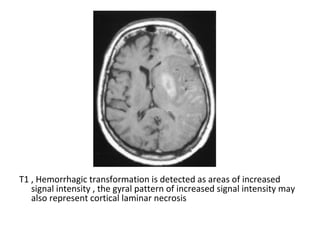

9-Hemorrhage :

-Hemorrhagic transformation is a little variably

used and collectively refers to two different

processes which have different incidence ,

appearance and prognostic implications ,

these are :

a) Petechial hemorrhage

b) In the case of secondary hematomas :

-The radiographic features on both CT and MRI are

merely a summation of the features of a ischemic

infarct with superimposed cerebral hemorrhage

-The amount of hemorrhage relative the size of the

infarct can vary widely but usually it is possible to

identify significant areas of the brain which are

infarcted but not hemorrhagic

-This may not be the case if the hemorrhage is large

and the underlying infarct small

-By the time secondary hematomas form , the

underlying infarct should be easily seen

and will appear as a region of low attenuation

involving both the white matter and the

overlying cortex

-Hemorrhage is often patchy , scattered

throughout the infarcted tissue and usually

represents only a small component of the

abnormal tissue

T1 , Hemorrhagic transformation is detected as areas of increased

signal intensity , the gyral pattern of increased signal intensity may

also represent cortical laminar necrosis

signal intensity